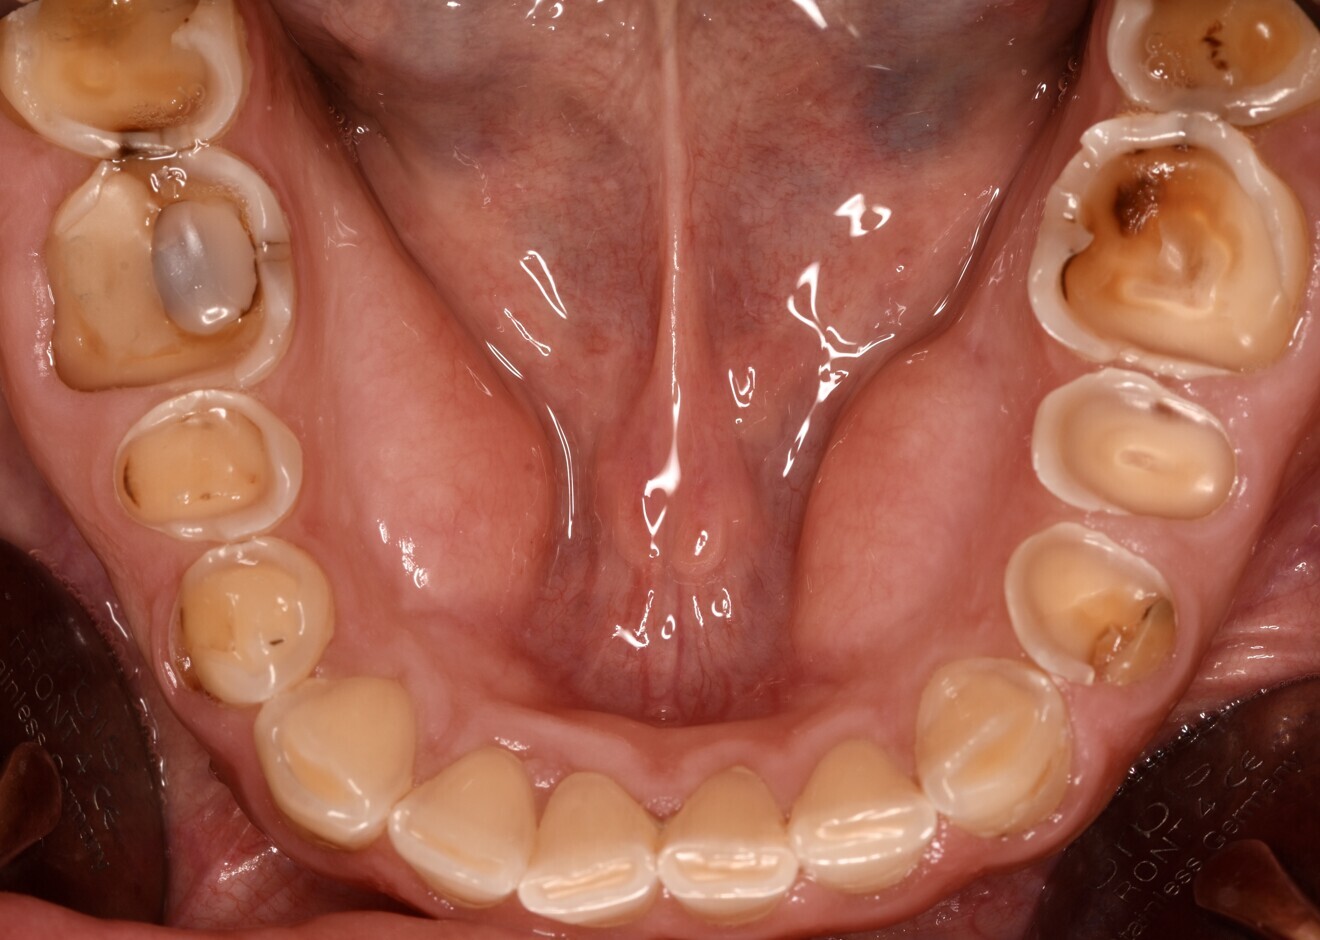

Fig. 1d: Almost complete loss of the occlusal relief in the upper jaw.